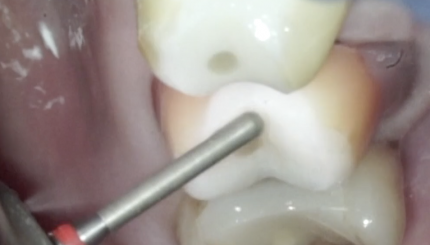

16 зуб . Билдап под оверлей